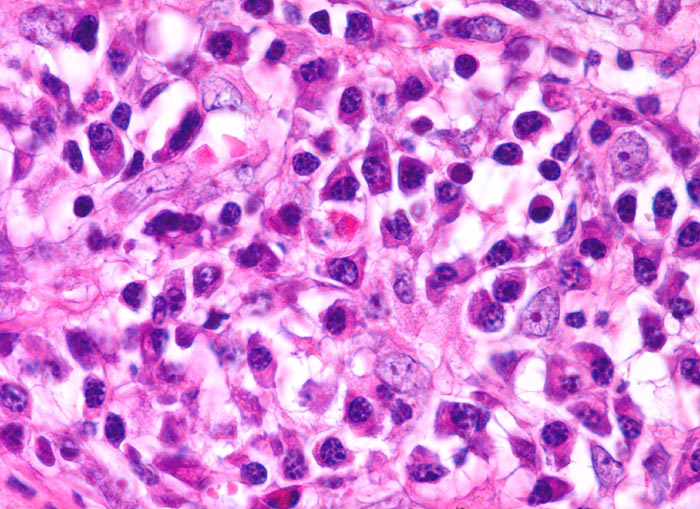

Morphologische Merkmale:

• Zerstörung der Lymphknotenarchitektur.

• Von breiten Bindegewebssträngen abgegrenzte Knoten.

• Die Knoten bestehen vorwiegend aus einem Mischzellinfiltrat reaktiver Zellen: Lymphozyten, Histiozyten, eosinophile Granulozyten und Plasmazellen.

• Reed-Sternbergzelle mit spiegelbildlich angeordneten Kernen mit sehr grossen eosinophilen Nukleolen.

• Einkernige Hodgkinzelle mit prominentem Nukleolus umgeben von einem Retraktionsartefakt (Lakunarzelle).